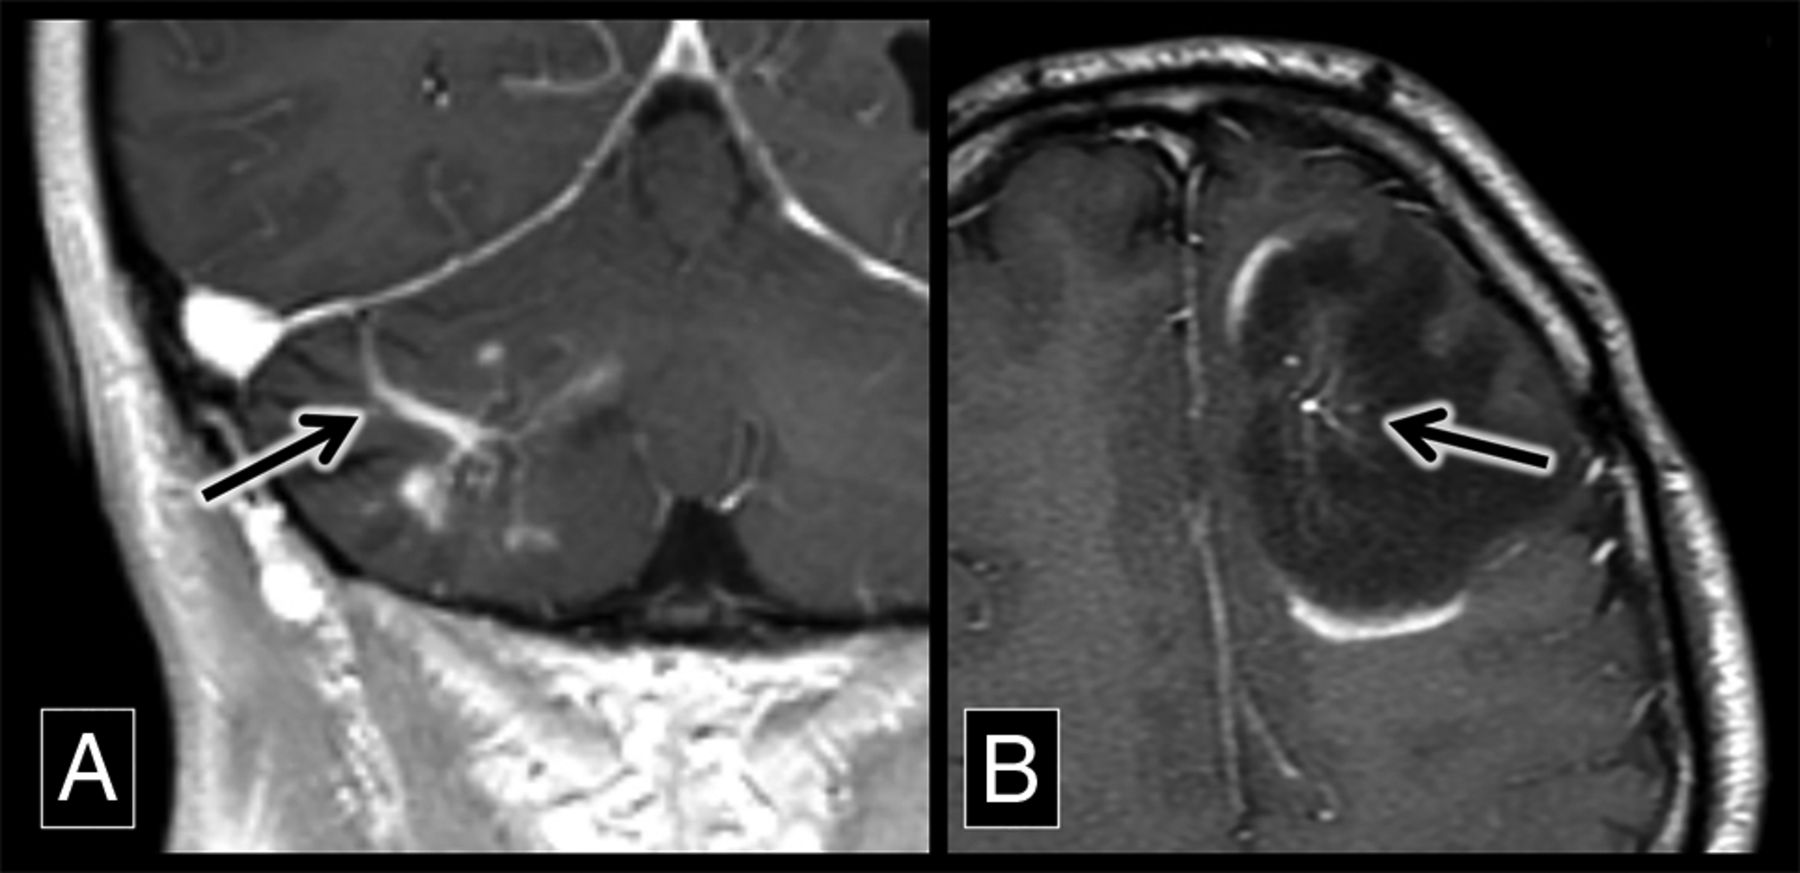

The association of DVAs with demyelination in patients with MS has clinical utility, particularly in cases in which there is imaging overlap between active demyelination and possible central nervous system neoplasms (Fig 3).14 A noninvasive diagnostic strategy in these cases is short-term follow-up imaging because the enhancement of an actively demyelinating lesion will fade with time, persisting chronically as a DVA-associated FLAIR hyperintensity. The association of DVAs and FLAIR hyperintensities in patients with MS can also be useful to explain why demyelinating plaques may appear in atypical locations such as the basal ganglia. MS plaques classically appear along normally distributed veins (such as at the callososeptal interface) but also can be seen in areas of the brain where there is variant venous anatomy.

Demyelinating lesions around developmental venous anomalies with enhancement. A, A coronal contrast-enhanced T1 sequence shows a superficially draining right cerebellar DVA (arrow) associated with enhancing parenchymal lesions. This was biopsy-proved demyelination. B, An axial contrast-enhanced T1 sequence shows a left frontal lobe DVA (arrow) with surrounding T1 hypointensity and discontinuous peripheral enhancement, typical of demyelination in a patient with MS.